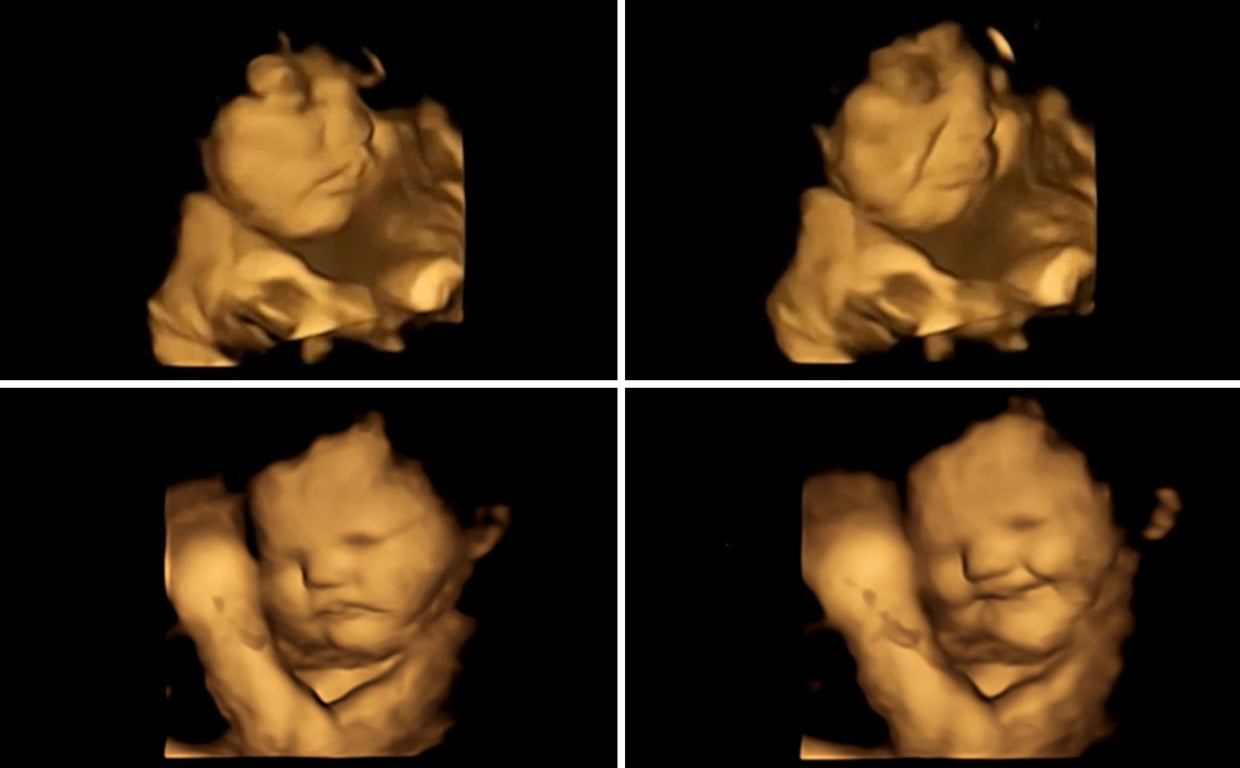

En concreto, los investigadores observaron cómo reaccionaban los fetos a los sabores de zanahoria o col rizada poco tiempo después de que las madres hubieran ingerido dichos alimentos. Los fetos expuestos a la zanahoria mostraron más respuestas de 'cara de risa', mientras que los expuestos a la berza mostraron más respuestas de 'cara de llanto'.

Las reacciones faciales observadas en ambos grupos de sabor, en comparación con los fetos en un grupo de control, que no estuvieron expuestos a ninguno de los sabores, mostraron que la exposición a solo una pequeña cantidad de sabor a zanahoria o col rizada fue suficiente para estimular una reacción.